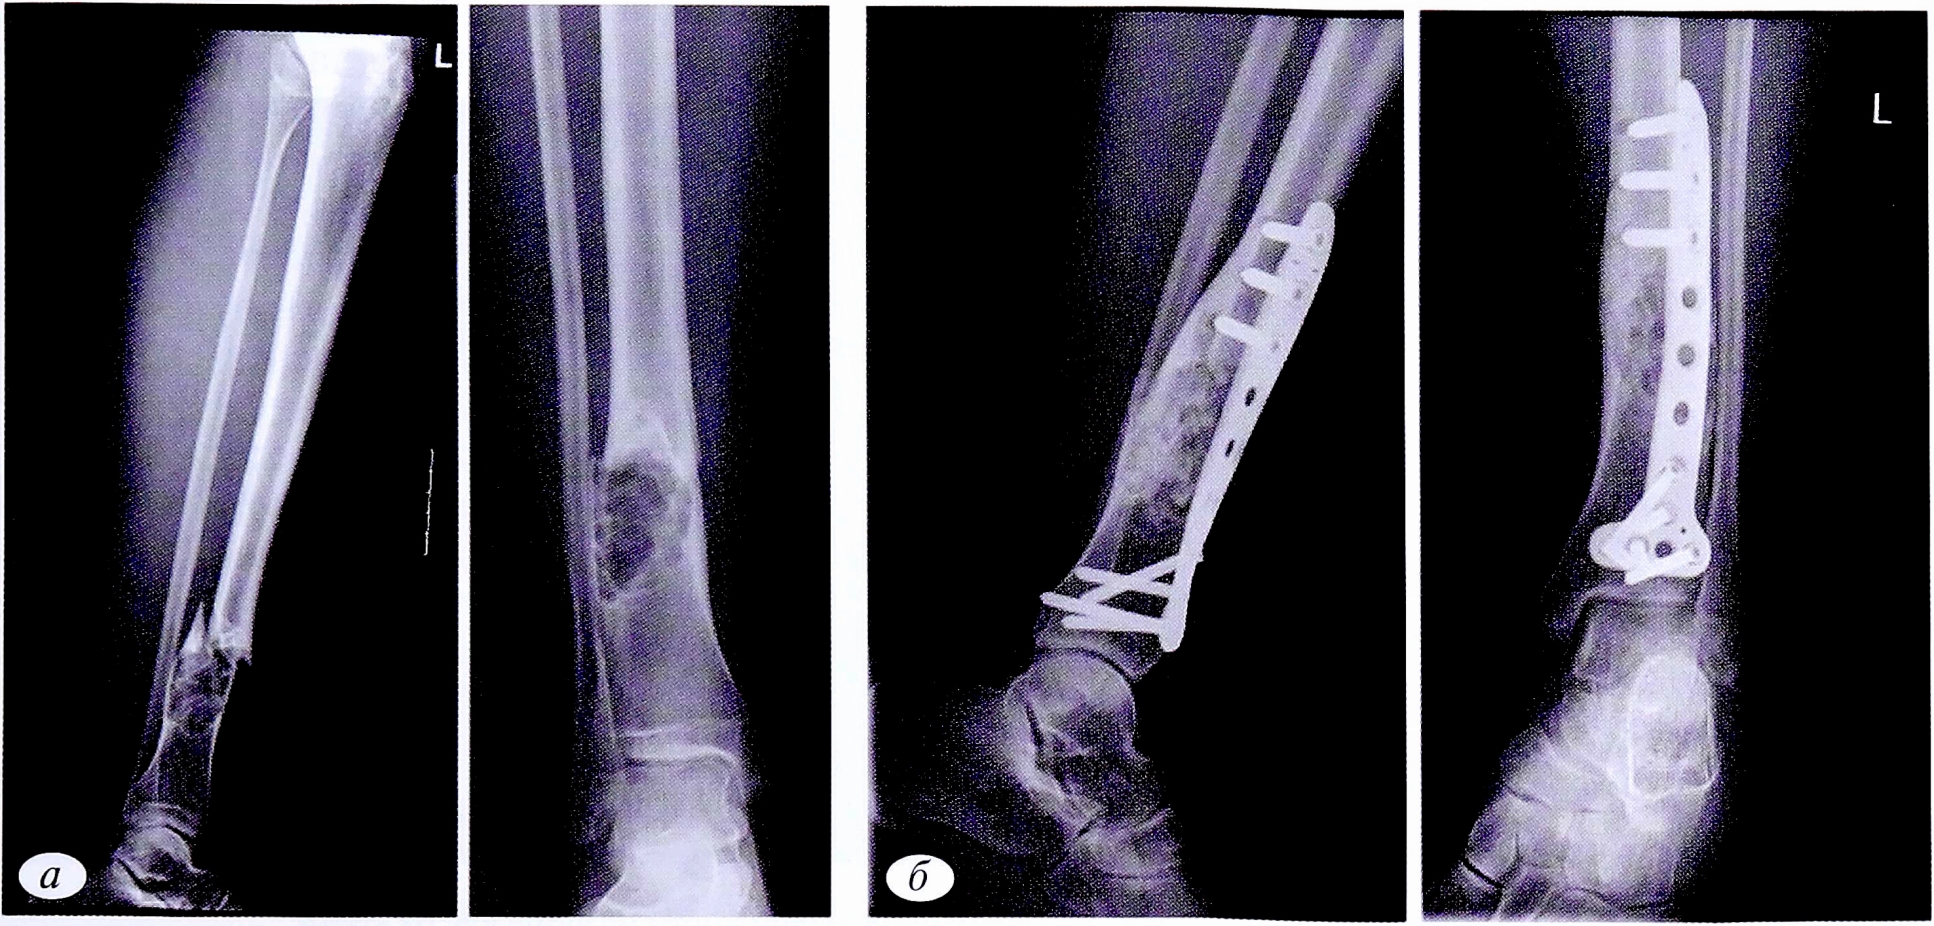

Рис. 4. Пациентка С.,16 лет. Диагноз: патологический перелом нижней трети левой большеберцовой кости на фоне неостеогенной фибромы. а — рентгенограммы костей левой голени в 2 проекциях до операции; б — после операции: открытая репозиция, краевая резекция нижней трети левой большеберцовой кости, аллопластика, металлоостеосинтез.

Fig. 4. Patient S.,16 years old. Diagnosis: pathological fracture of the lower third of the left tibia due to non-osteogenic fibroma. a — radiographs of the bones of the left tibia in 2 projections before surgery; б — radiographs of the bones of the left lower leg after surgery: open reduction, marginal resection of the lower third of the left tibia, alloplasty, metallosteosynthesis.